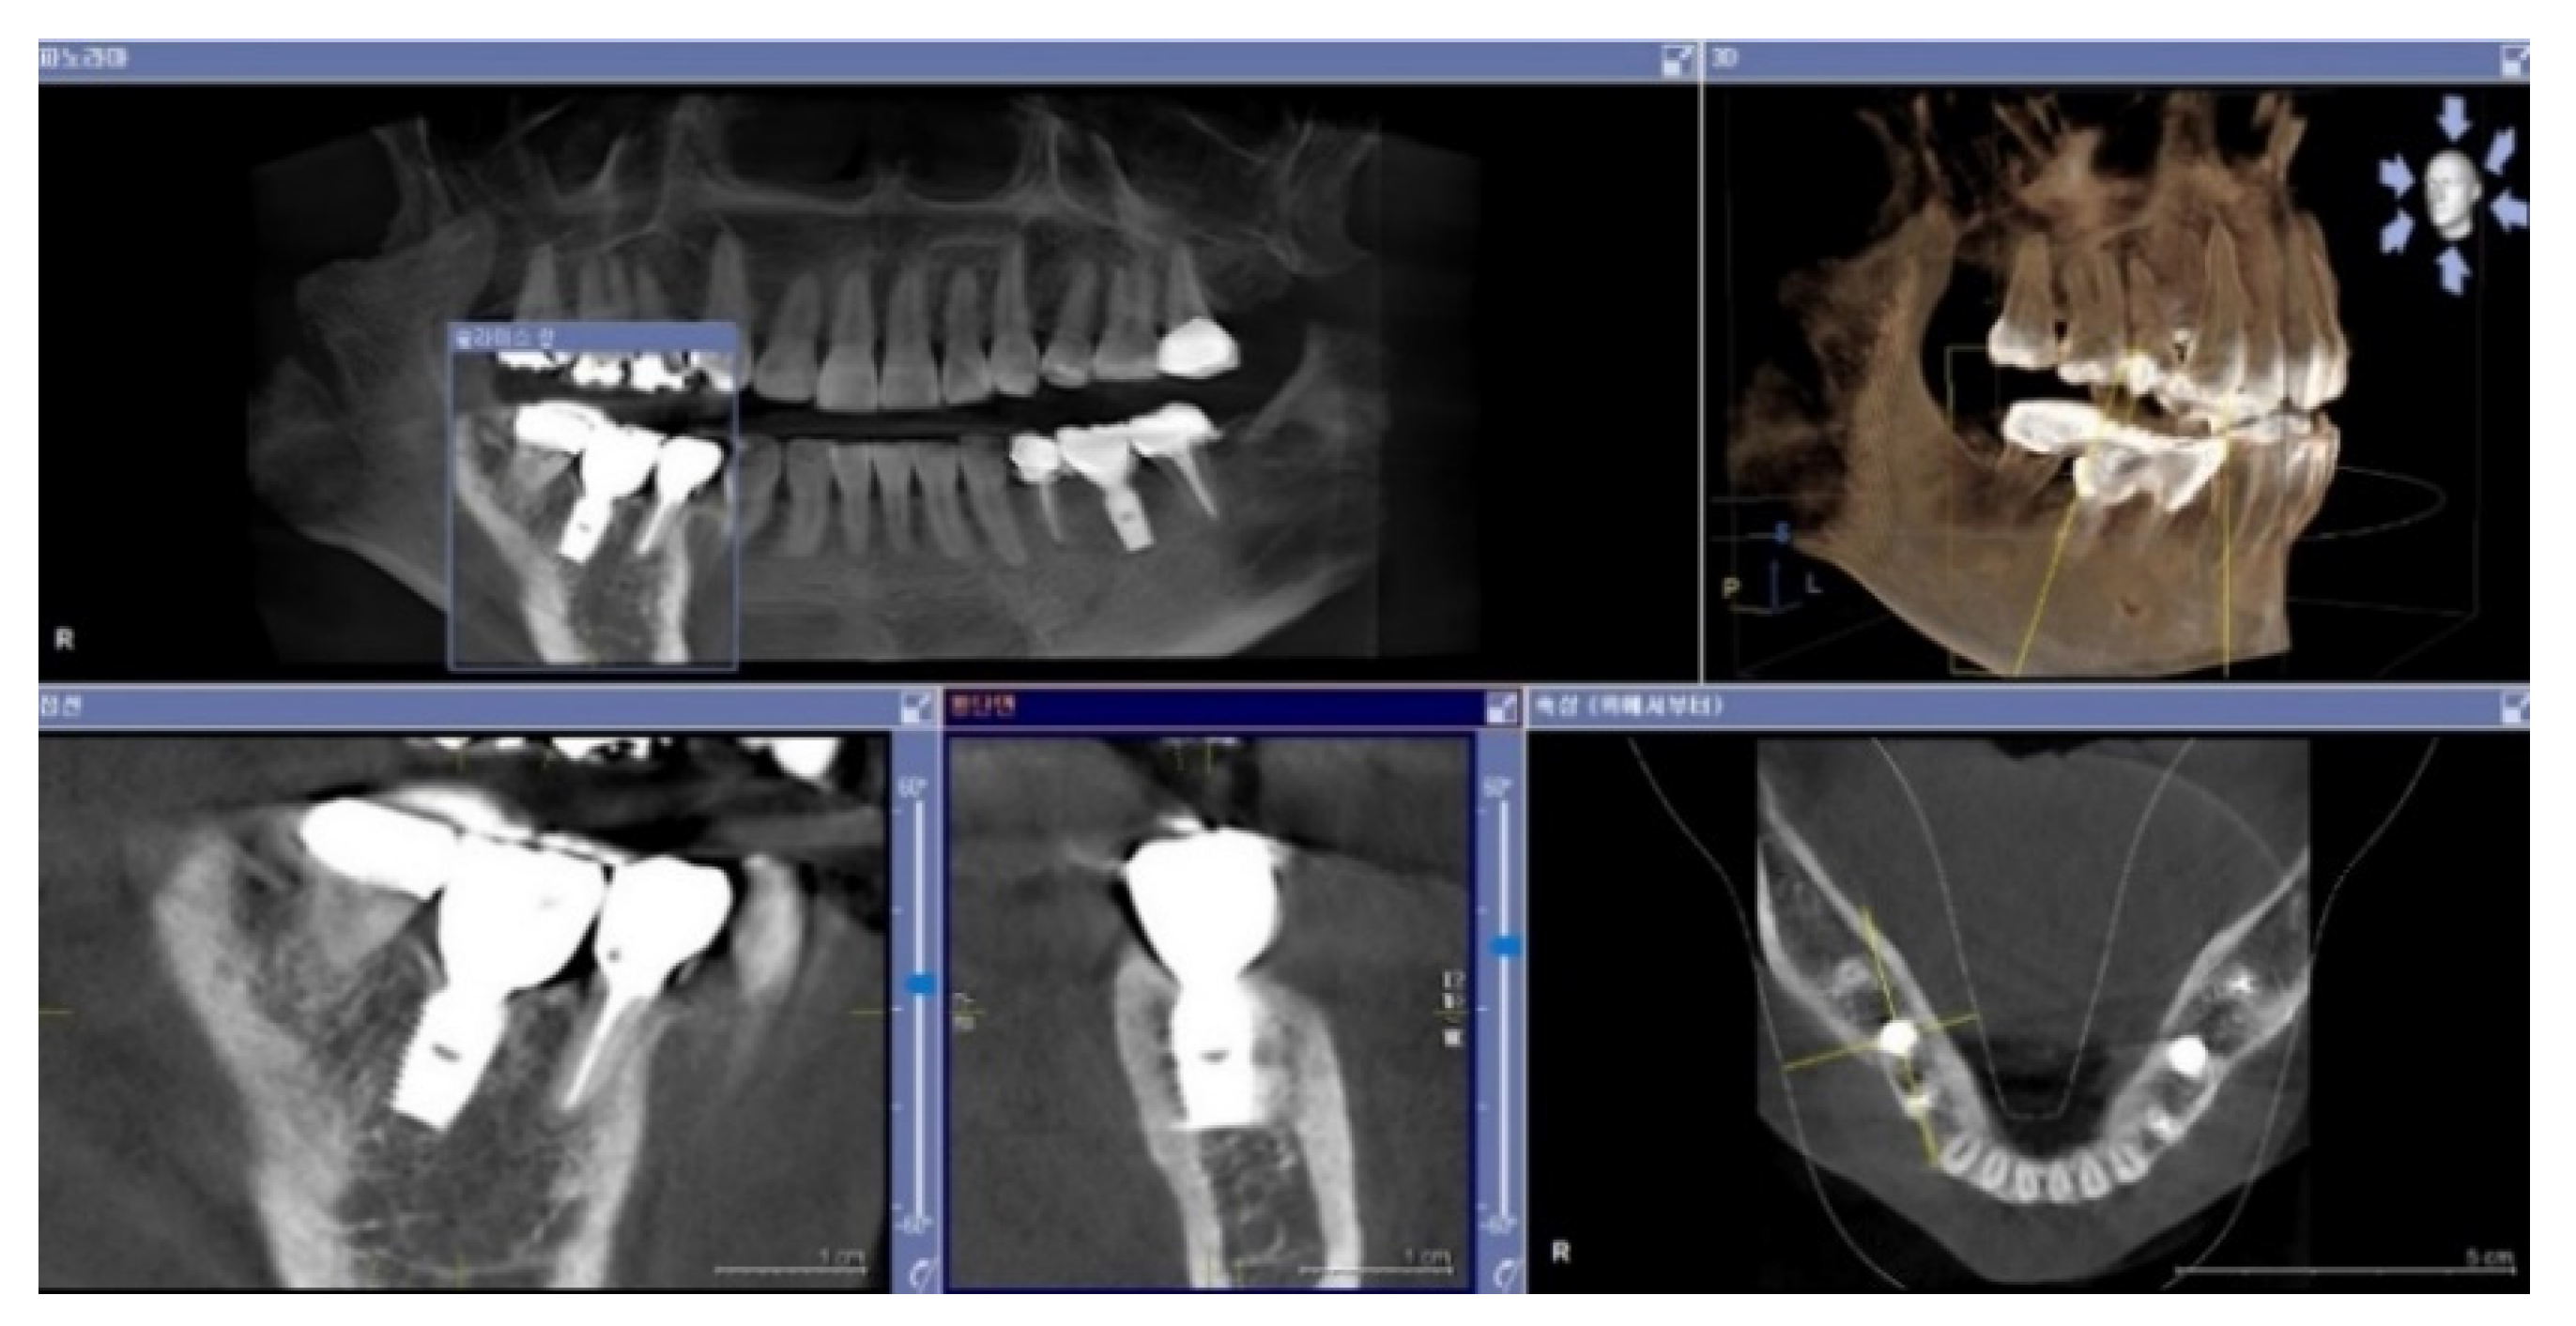

Figure 5. This figure illustrates a case where a plain X-ray image suggests that the implant was placed subcrestally, but a CBCT (Cone Beam Computed Tomography) image reveals that the fixture was actually placed epi-crestally in the buccolingual aspect.

Typically, a plain X-ray (panoramic view, or standard oral) is recommended for routine follow-up examinations to assess the outcomes of implant placements. However, using plain X-rays to observe the depth of an implant fixture and to study its relationship with surrounding tissues (bone and soft tissue) is limited, as this imaging modality only provides information on the mesiodistal relationship. Occasionally, while plain X-rays may indicate that implant fixtures are placed very deep, further examination using Cone Beam Computed Tomography (CBCT) can reveal that the buccal depth of implant placement is actually epi-crestal.

In this study, images from CBCT reviews were utilized for a 3-dimensional analysis to investigate not only the mesiodistal aspects but also the buccal and lingual sides, examining the relationship between the artificial implant complex (implant fixture, abutment, and crown) and the biological tissues (bone and soft tissue).